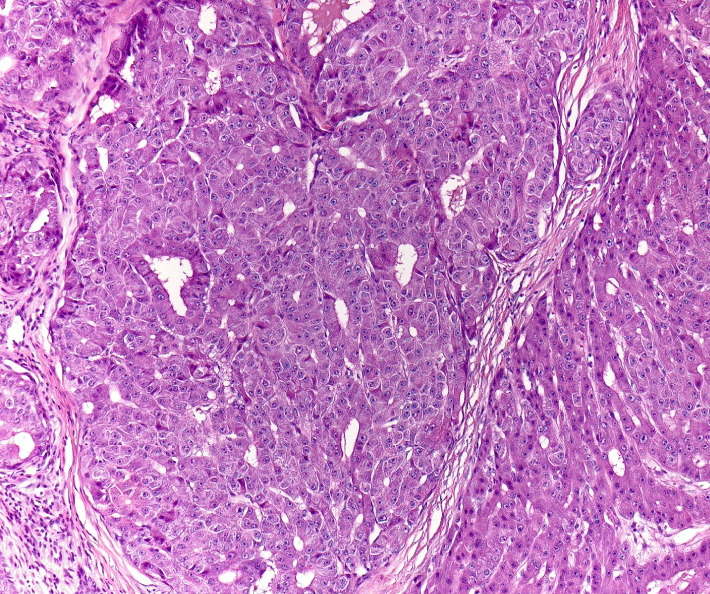

Introduction: Cutaneous metastases of hepatocellular carcinoma (HCC) are uncommon but important to recognize for timely diagnosis and management. Case Presentation(s): We present a case of a 70-year-old man with a history of HCC who developed a painless nodule on the scalp. Histopathological examination and immunohistochemistry confirmed the nodule as cutaneous metastasis of HCC. The patient had previously undergone transarterial chemoembolization and surgery for HCC, with no evidence of disease for a period before presenting with the cutaneous lesion. Conclusion: Cutaneous metastasis of HCC is rare but signifies advanced disease. This case underscores the importance of considering cutaneous manifestations in patients with a history of HCC and highlights the need for routine follow-up and early intervention to improve patient outcomes.